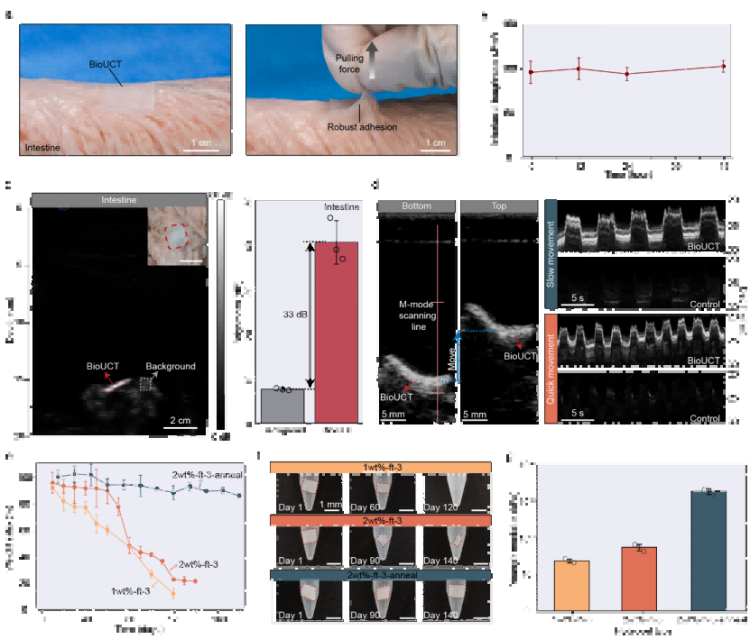

圖1. 用于超聲對比成像的BioUCT設計。

①革命性成像性能:從“看不見”到“高清追蹤”超強聲學反射(圖2a-b)通過周期性微氣囊設計,BioUCT在體外測試的2MHz超聲下實現57dB頻譜信號增幅(較普通水凝膠),在實際動物實驗中將B超圖像亮度提升30dB,使腸道輪廓清晰顯現(圖2b)。時/頻域分析顯示其回聲強度遠超軟組織(圖2a),解決了腸道超聲的信噪比受腸道“弱反射”限制的核心痛點。

抗形變穩定性(圖2f-g)在50%拉伸及90°彎曲狀態下(模擬腸道蠕動),B超/M超成像亮度波動<5%(圖2f),相位監測波形穩定(圖2g),確保動態監測可靠性。

大角度成像能力(圖2c-e)探頭在深度(5-25cm)、角度(±30°)、水平位移(±20mm)變化時,圖像亮度標準差<1.5dB(*n*=3),適配臨床操作誤差。

圖2. BioUCT的超聲對比成像性能。

② 智能生物適配:像“第二層生物表皮”一樣工作強力粘附與抗脫落(圖3a-b)離體豬腸實驗證實,BioUCT與腸壁界面韌性達200 J/m2(相當于外科縫合強度),48小時內粘附穩定性>95%(圖3b)。拉力測試中可承受10N以上牽拉(圖3a),遠超腸道蠕動產生的生理應力(通常<2N)。

精準降解調控(圖3e-g)通過調節PVA/CMC水凝膠結晶度,實現10%-90%的可控降解速率(120天內),且降解過程中楊氏模量保持15-35kPa(圖3g),始終匹配軟組織力學特性,避免器官損傷。

圖3. BioUCT的離體展示。

③ 離體驗證臨床價值:動態追蹤不再是難題顯著提升診斷靈敏度(圖3c-d)貼附BioUCT的離體豬腸在B超圖像中亮度提升33dB(圖3c),相當于將傳統超聲的“模糊陰影”變為“高清影像”。M超動態成像成功捕捉模擬腸蠕動軌跡(圖3d),為量化腸道運動提供新工具。跨器官普適性(補充圖18)在豬心、胃等器官同樣實現>30dB亮度提升,證實技術可擴展性。